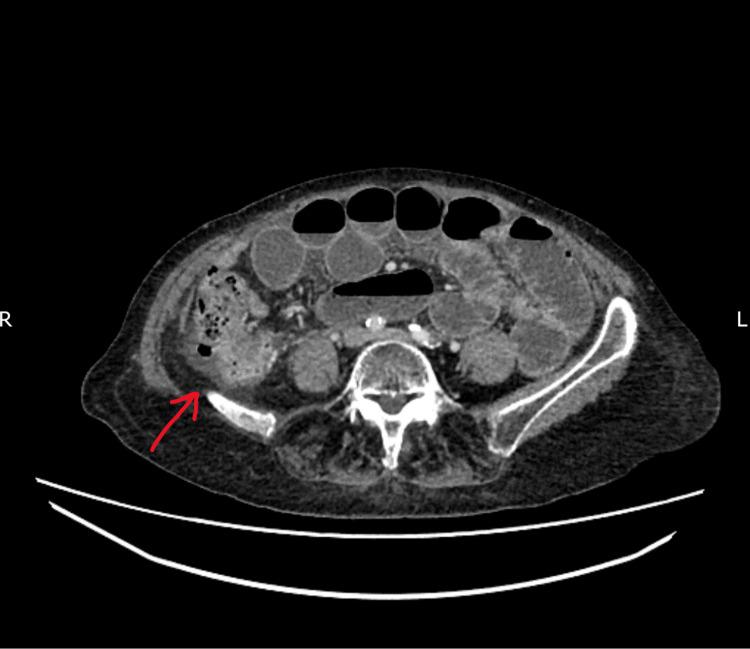

Para-caecal hernias are a rare type of internal hernias. They can cause bowel obstruction, leading to strangulation of the bowel. As such, urgent diagnosis and appropriate management are important. Both laparoscopic and open approaches are options in terms of surgical treatment. We report a case of a para-caecal hernia causing small bowel obstruction and highlight the laparoscopic approach as a feasible and effective way of management.